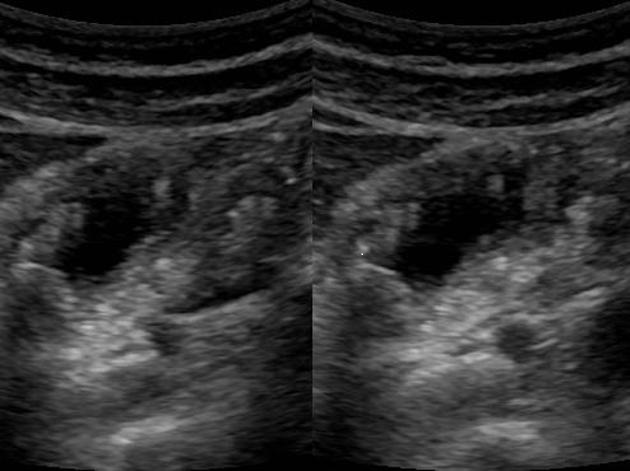

Image echographique d'une polyp

adenomateuse de type sessile supracentimetrique (

fleche rouge ) |

|